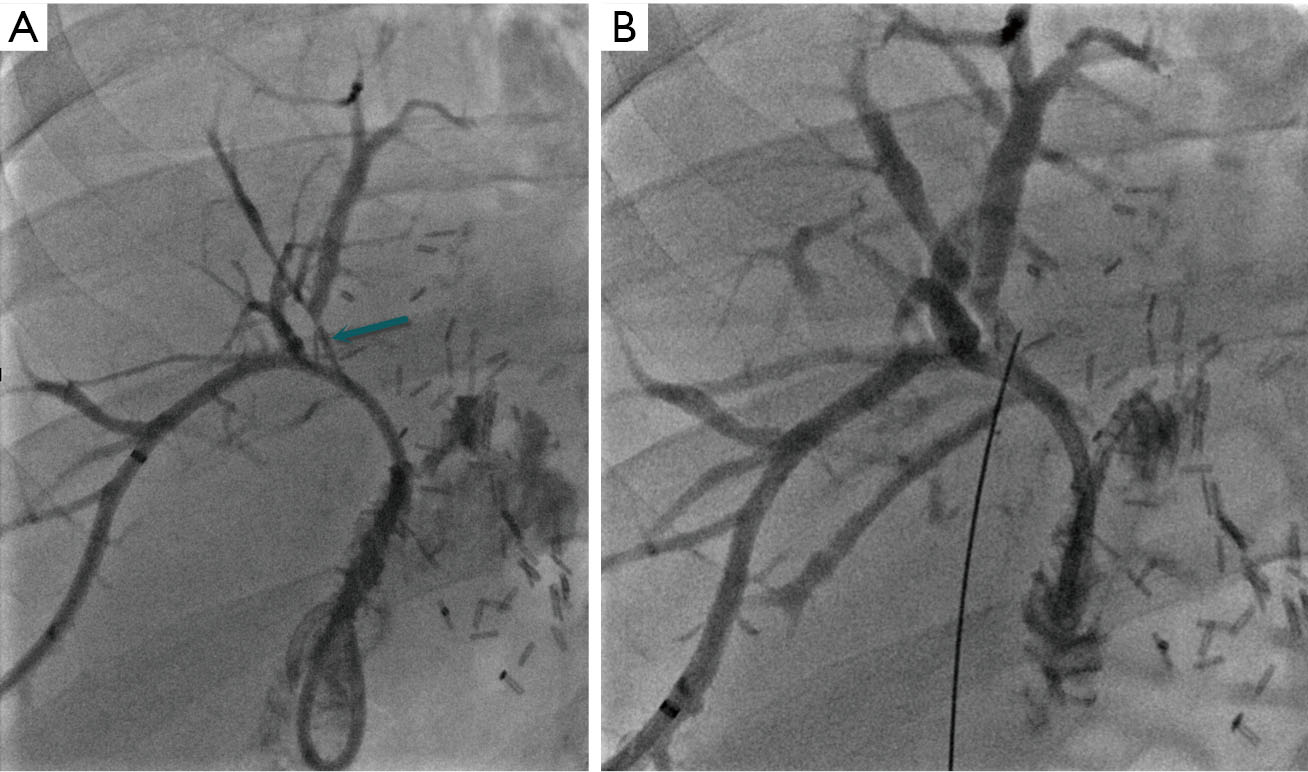

Фотографии и изображения, связанные с симптомами первичного склерозирующего холангита